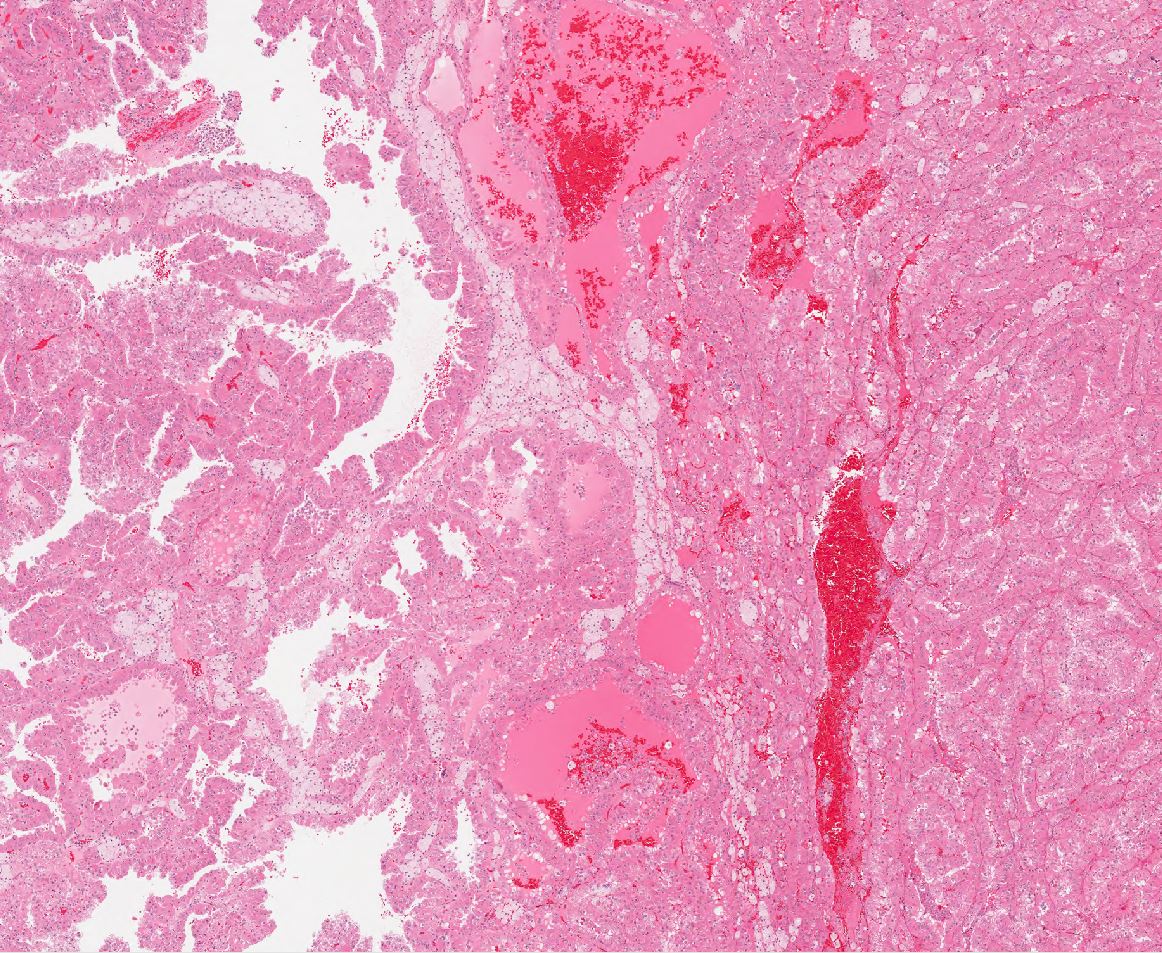

Renal tumor grading

Case ID: 564